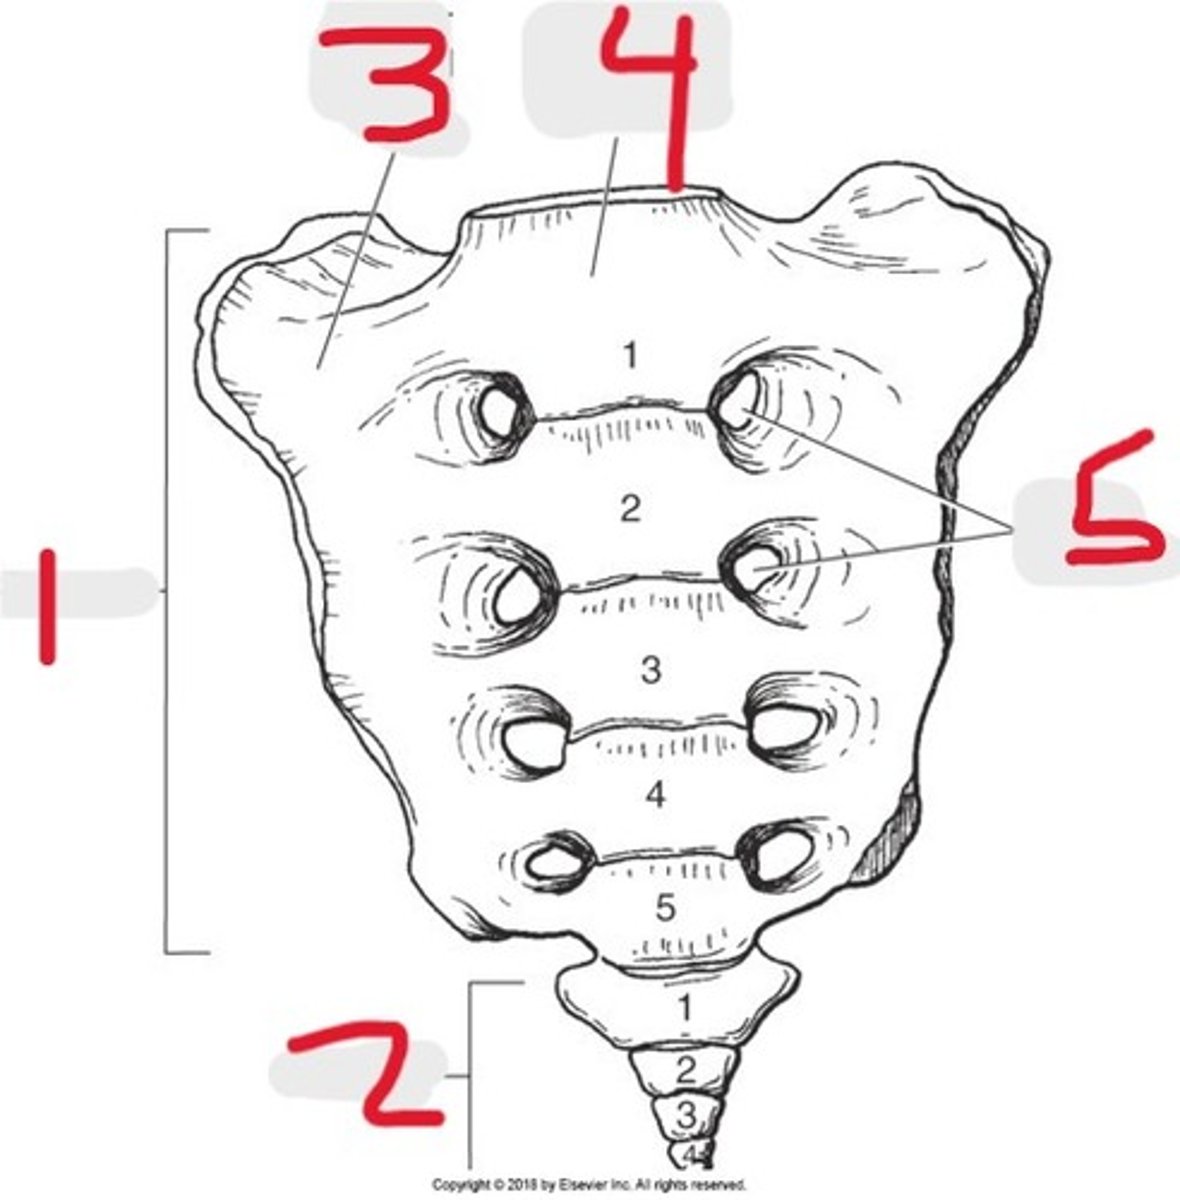

1) Sacrum

2) Coccyx

3) Ala or lateral mass

4) Body of 1st sacral segment

5) Sacral promontory

6) Sacral foramina

Name all numbered structures

1) Lateral mass

2) Sacral foramina

3) Body

4) Sacrum

5) SI joint

6) Sacral promontory

7) Ilium

Name all numbered structures